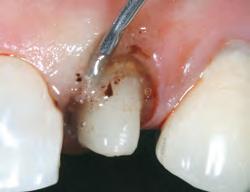

1. Subgingival preparation with bleeding. BLEEDING HEMOSTASIS

2. Scrub Astringedent™ X hemostatic firmly against bleeding tissues with Metal DentoInfusor™ tip.

CLEANING/TESTINGDISPLACEMENT

3. Firm air/water spray removes residual

and tests tissue for quality, profound hemostasis.

Remove

4. Soak Ultrapak™ knitted cord in Astringedent™ X hemostatic, pack, and leave for 5 minutes.